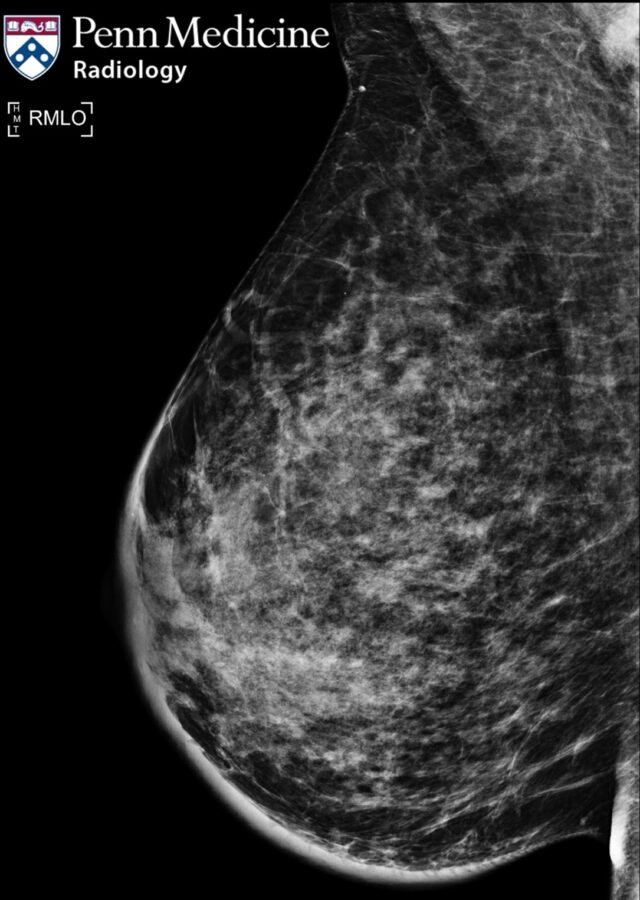

A 47-year-old premenopausal woman presented with lower abdominal discomfort and was initially monitored for a suspected uterine leiomyoma.